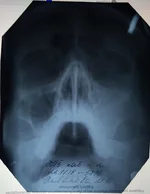

Вот решила к другому сходить врачу(в той же поликлиннике), он сделал снимок,увидел в носу какие то искривления, бугорок, говорит ей гайморит , надо пробивать чистить и т.д.. Вот тут Я совсем не понял, как врачи наши лечат(один одно,другой другое), решил проконсультироваться немного. Что нам делать и как поступить?

снимок прикрепил, скажите по нем видно чтото?

Забыл, есть старое еще фото 2010года( прикрепил)